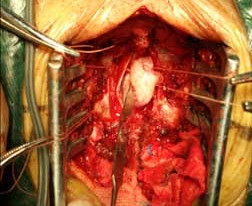

三叉神經(jīng)微血管減壓手術(shù)切口

術(shù)中顯微鏡鏡下神經(jīng)顯露